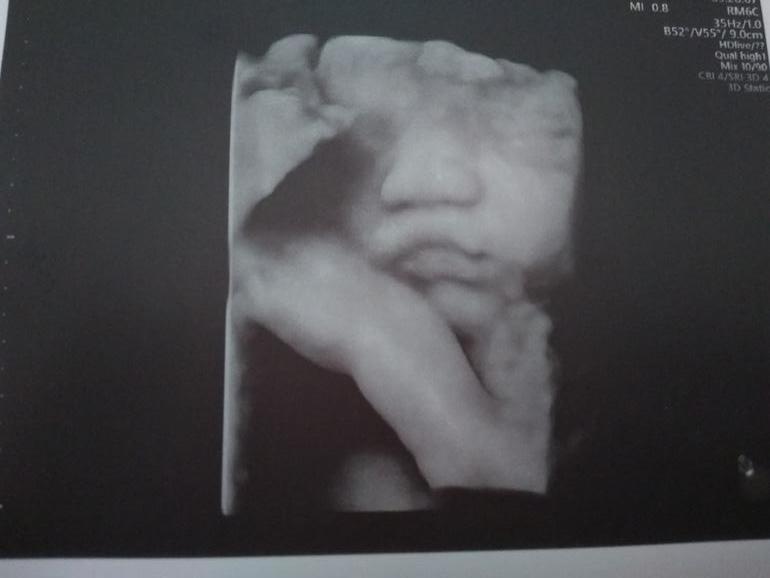

Из приятного. Сходили с мужем на 3д-узи. Малыш здоров, но процедуру традиционно проспал :) Сын немного дал себя рассмотреть, но фотогеничность - это не про него :)

А потом он засунул в рот палец и для верности закрылся ногой :) Разбудить его не смогли. Шоколадка не подействовала, переворачивание с боку на бок тоже и даже тычки датчиком оказались бесполезны. (Вот бы и после рождения он так крепко спал 😁)